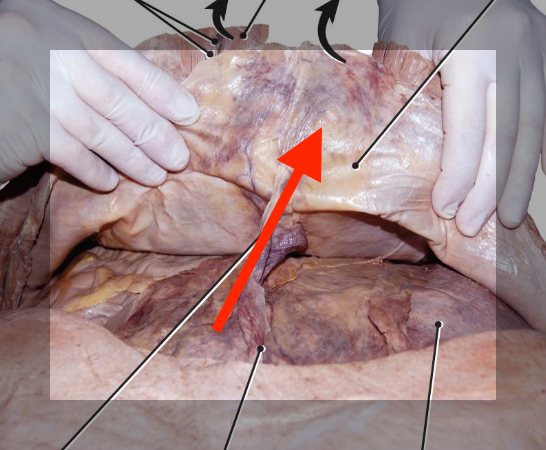

parietal peritoneum

lines the abdominal cavity

viceral peritoneum

A: the inner layer the surround organs

falciform ligament

greater omentum

peritoneal cavity

greater sac

peritoneal compartment of the abdominal cavity

lesser sac

peritoneal pouch located behind the lesser omentum and stomach